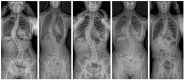

Results: A total of 126 adolescent idiopathic scoliosis patients were included, with a mean preoperative Cobb angle of 64.5° (range, 45°-112°). Reported pain prevalence was 34.1%. Pain and no-pain groups were very different in their self-reported experience, with a very low mean visual analogue scale score of 0.5 (± 0.6) in the no pain group, while visual analogue scale averaged 5.6 (± 1.2) in the pain group (p < 0.001). No significant difference was found between groups regarding the most relevant demographic and radiological parameters.